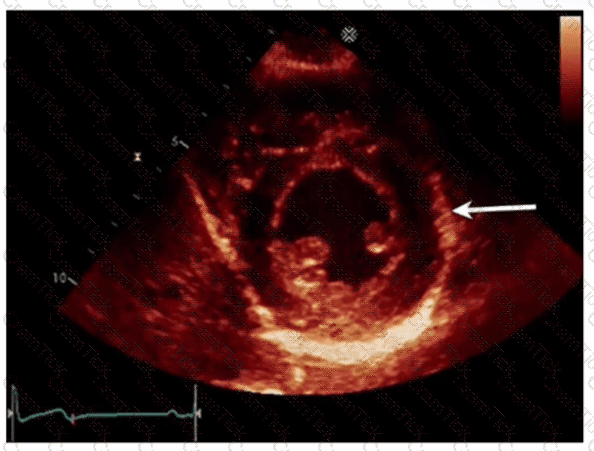

Which left ventricular regional wall segment is indicated by the arrow on this image?

Which condition is most plausible based on the finding indicated by the arrow on this image?